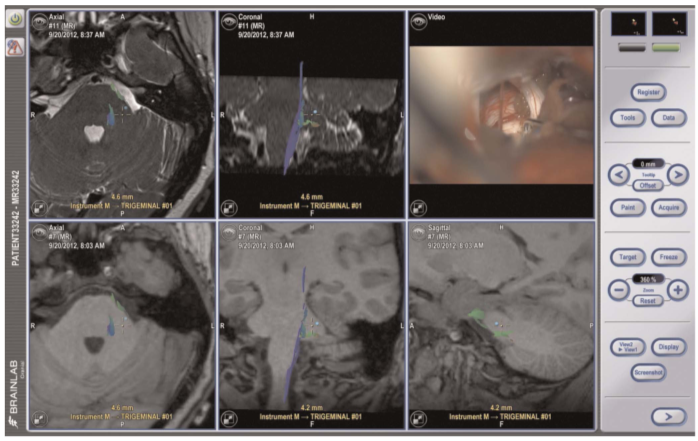

There was no arterial compression of the left trigeminal nerve shown on a brain MRI with diffusion tensor imaging (DTI) sequences. The decision was made to take her to surgery for a left-sided microvascular decompression (MVD) and possible tractotomy via a retrosigmoid approach. At surgery, a compressing vein over the dorsum of the left trigeminal nerve was noted and dissected off the nerve; a muscle graft was gently wedged in place to separate the vein from the nerve. No convincing arterial compression was found. A tractotomy of the descending nucleus of the trigeminal nerve was performed using stereotactic neuronavigation and microscopic visualization of the inferior aspect of the trigeminal nerve root entry zone; the preferred entry point for the VPT procedure is 1mm inferolateral to this point (Figure 1).

Low power micro-bipolar electrocautery is used to incise the pia and a 6-8 mm right-angled microdissector (tracked by the neuronavigation system) is used to enter into the brainstem to a depth of 7-9 mm in a plane parallel to the trigeminal nerve proceeding dorsomedially to the descending spinal tract of the trigeminal nerve (Figure 1). Neuronavigation is used to guide the microdissector 2-3 mm along the inferior aspect of the pontine descending trigeminal pathway. This action facilitates the disruption of the spinal tract of the trigeminal nerve superior to the point at which it converges into a vertical compact tract (Figures 1 and 2). The anterolateral corner of the rhomboid fossa and fourth ventricular floor plane is used to guide the trajectory of the microdissector (Figure 2).